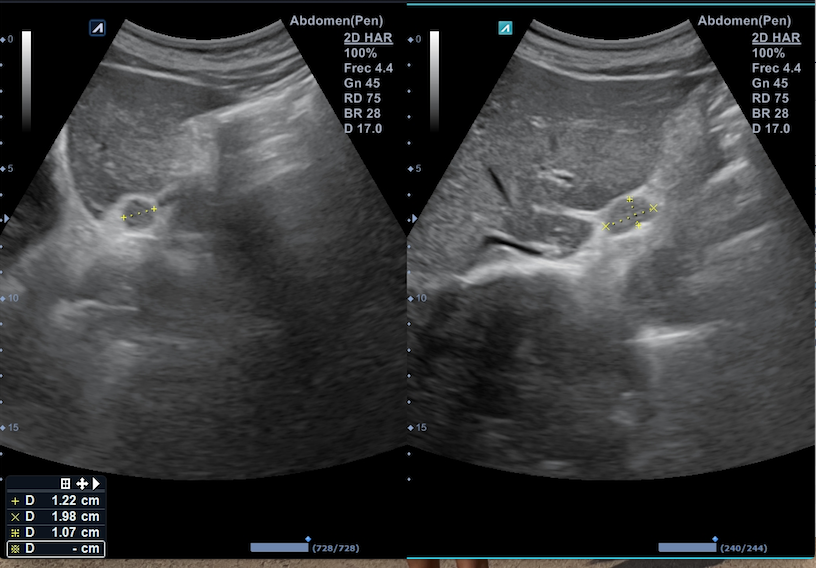

Citamos en consulta para realizar ecografía abdominal destacando a la exploración la presencia de 3 formaciones en retroperitoneo superior, en zona subdiafragmática y mediales al hiato aórtico: la primera a la derecha del tronco celiaco, de aspecto ovalado e isoecogénico de 1,2 x 1,9 cm; la segunda en línea media, debajo del lóbulo caudado, de aspecto hipoecogénico y con zona central de menor densidad de 1,9 x 2,2 cm; la tercera, a la izquierda de esta última de 2,2 x 2,8 cm sugerentes de adenopatías retroperitoneales.